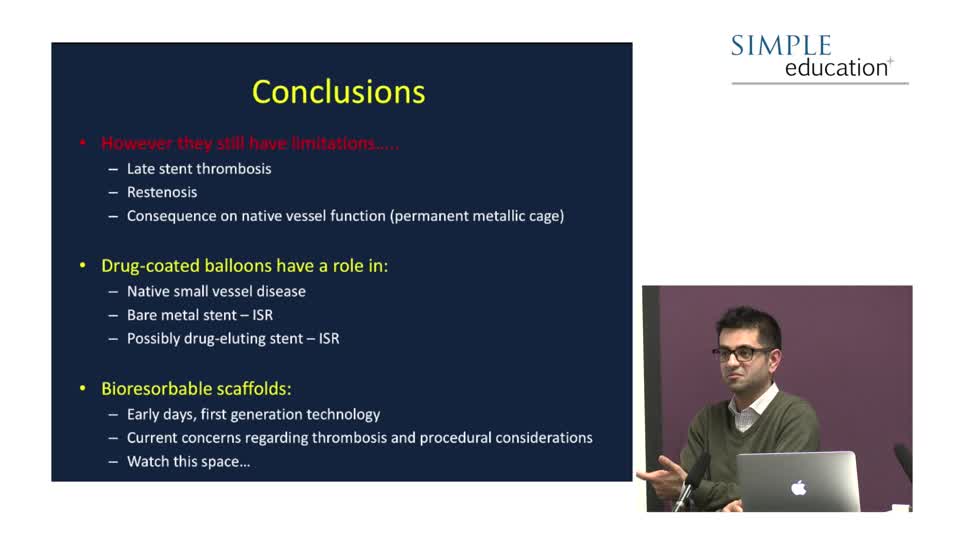

Essential Guide to Stents, Bioabsorbable Vascular Scaffolds & Drug Elution Balloons - Let's Make Things Simple - Dr. Neil Ruparelia